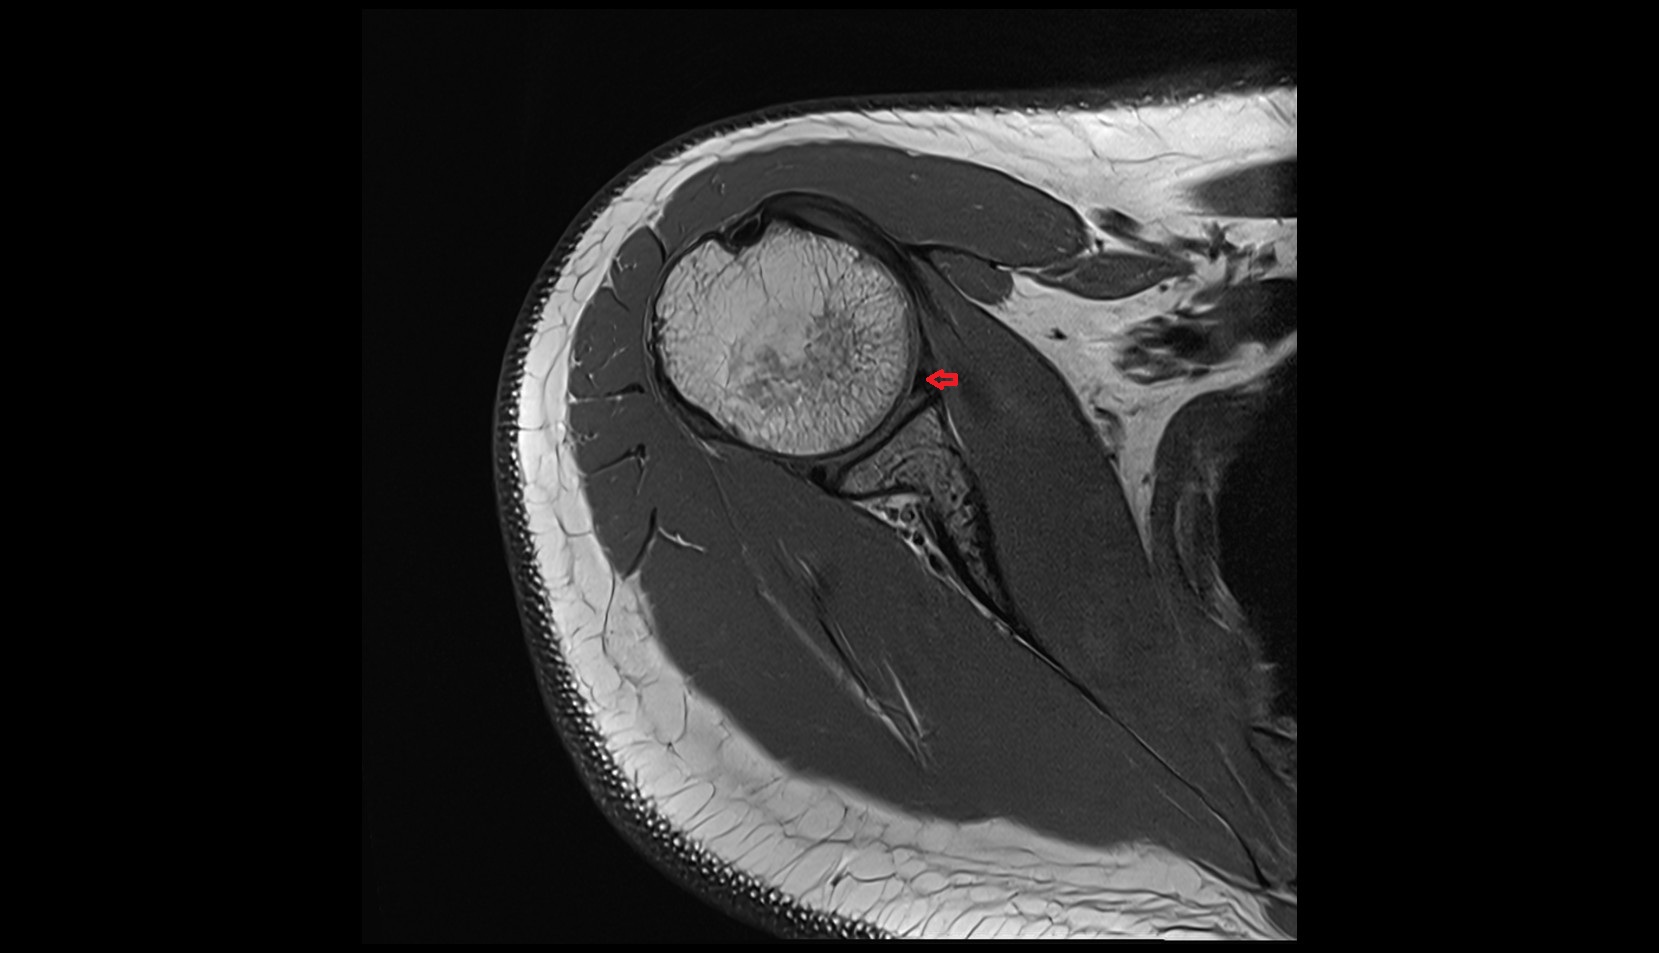

- Shoulder joint (glenohumeral joint)

- Supraspinatus tendon

- Glenoid labrum

- Glenohumeral joint capsule